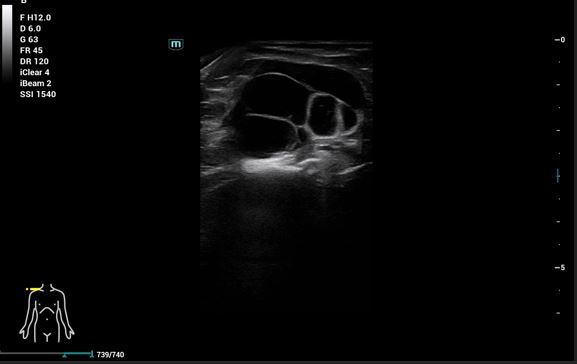

Se realiza ecografía hombro derecho para ayudarnos con el diagnóstico diferencial: tumores sólidos, quistes o gangliones de contenido líquido.

Ecografía de hombro derecho: Lesión multilobulada anecoica, sin claro refuerzo posterior, bien delimitada con paredes gruesas. Doppler negativo.

RMN: Cambios hipertróficos en la articulación acromio-clavicular con líquido e imagen de ganglión de unos 5 cm. Desgarro del manguito de los rotadores con desgarro completo del tendón supraespinoso. Desgarro del tendón infraespinoso, del tendón subescapular, del redondo menor y del tendón de la cabeza larga del bíceps braquial. Líquido en la bolsa subacromiosubdeltoidea y subcoracoidea.